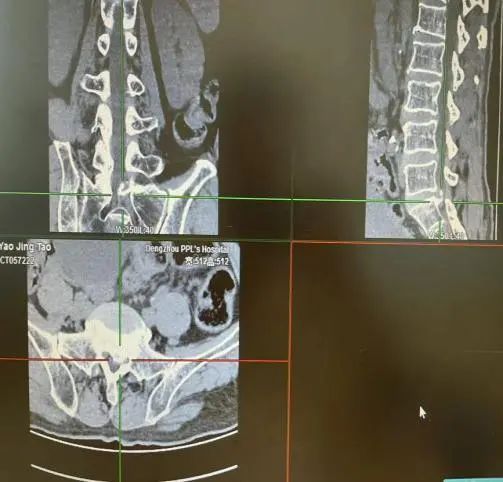

今年50岁的市民姚先生,腰腿疼痛已经一年多了,一直保守治疗,但效果不理想,总是反复发作,近期疼痛加重,稍走几步就感到下肢麻木剧痛,导致卧床不起,生活无法自理,苦不堪言。姚先生来到了邓州市人民医院骨外科三病区就诊。经过系统检查,姚先生腰5棘突叩击疼阳性,左下肢拖拽步态,踝关节背伸无力,小腿后方痛觉过敏,直腿抬高试验强阳性。 诊断为:1.腰5骨骶1椎间盘突出伴坐骨神经痛。核磁检查显示:腰椎退行性改变;L3—4、L4—5椎间盘膨出;L5S1椎间盘脱出(偏左);腰椎后方棘间筋膜炎。

“考虑到患者腰5/骶1椎间盘突出,髓核游离到狭窄的椎管内,开放手术因手术创伤大,视野欠佳,可能会有髓核的残留,导致术后症状不能完全缓解。”经过科室主任王志强和主治医生刘孟孟的综合评估、判定,决定采用更精准、高效且易操作的“单边双通道脊柱内镜下腰5/骶1髓核摘除术(UBE)”。